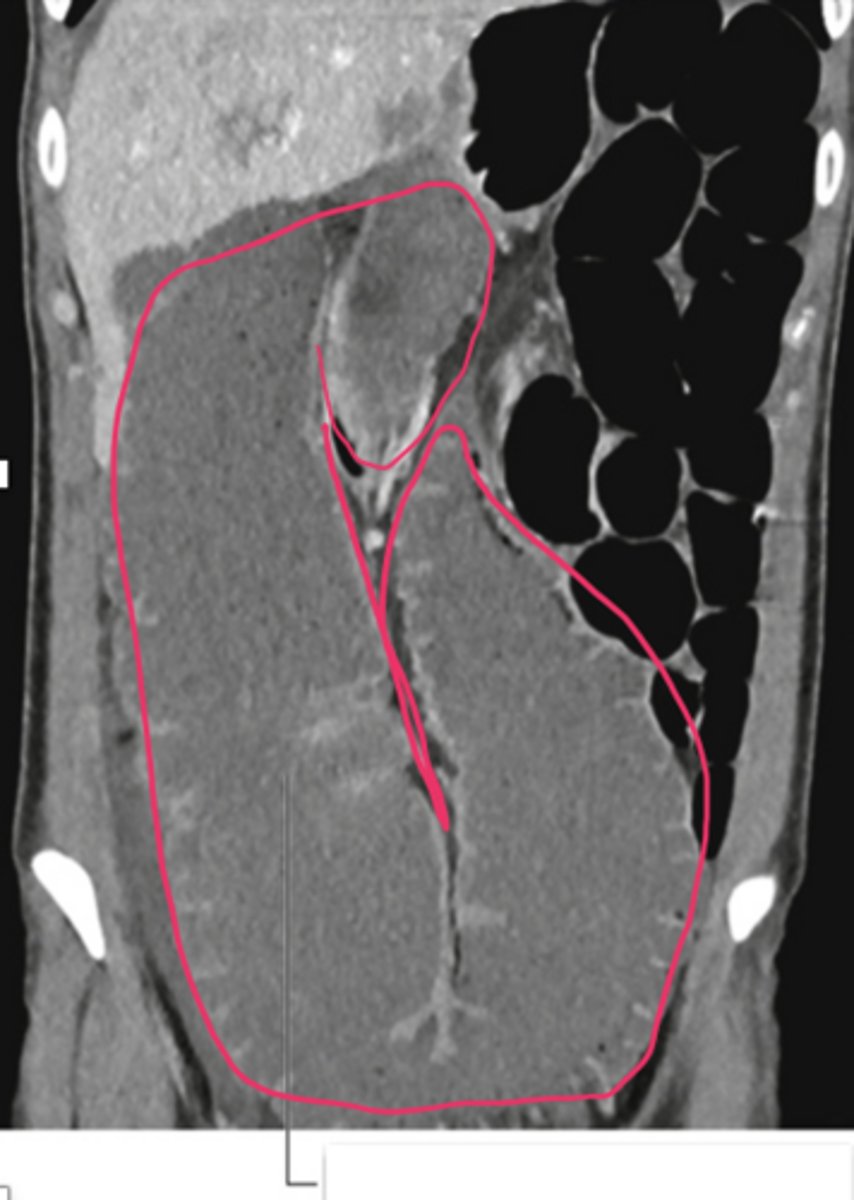

What are the lobes of the liver?

right (largest), left, caudate, quadrate

What is the bare area of the liver?

posterior section of the liver against the diaphragm that is bare without peritoneal covering

What impressions are found on the posterior view of the liver?

Gastric, colic, renal and suprarenal impression